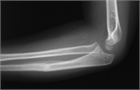

1. 尺骨骨折があった場合、橈骨頭脱臼を見流さないことがポイントである。

1. 見逃された陳旧例では前腕の回旋運動と肘の屈伸運動が障害される可能性があるため、できるだけ早く専門医に紹介する。